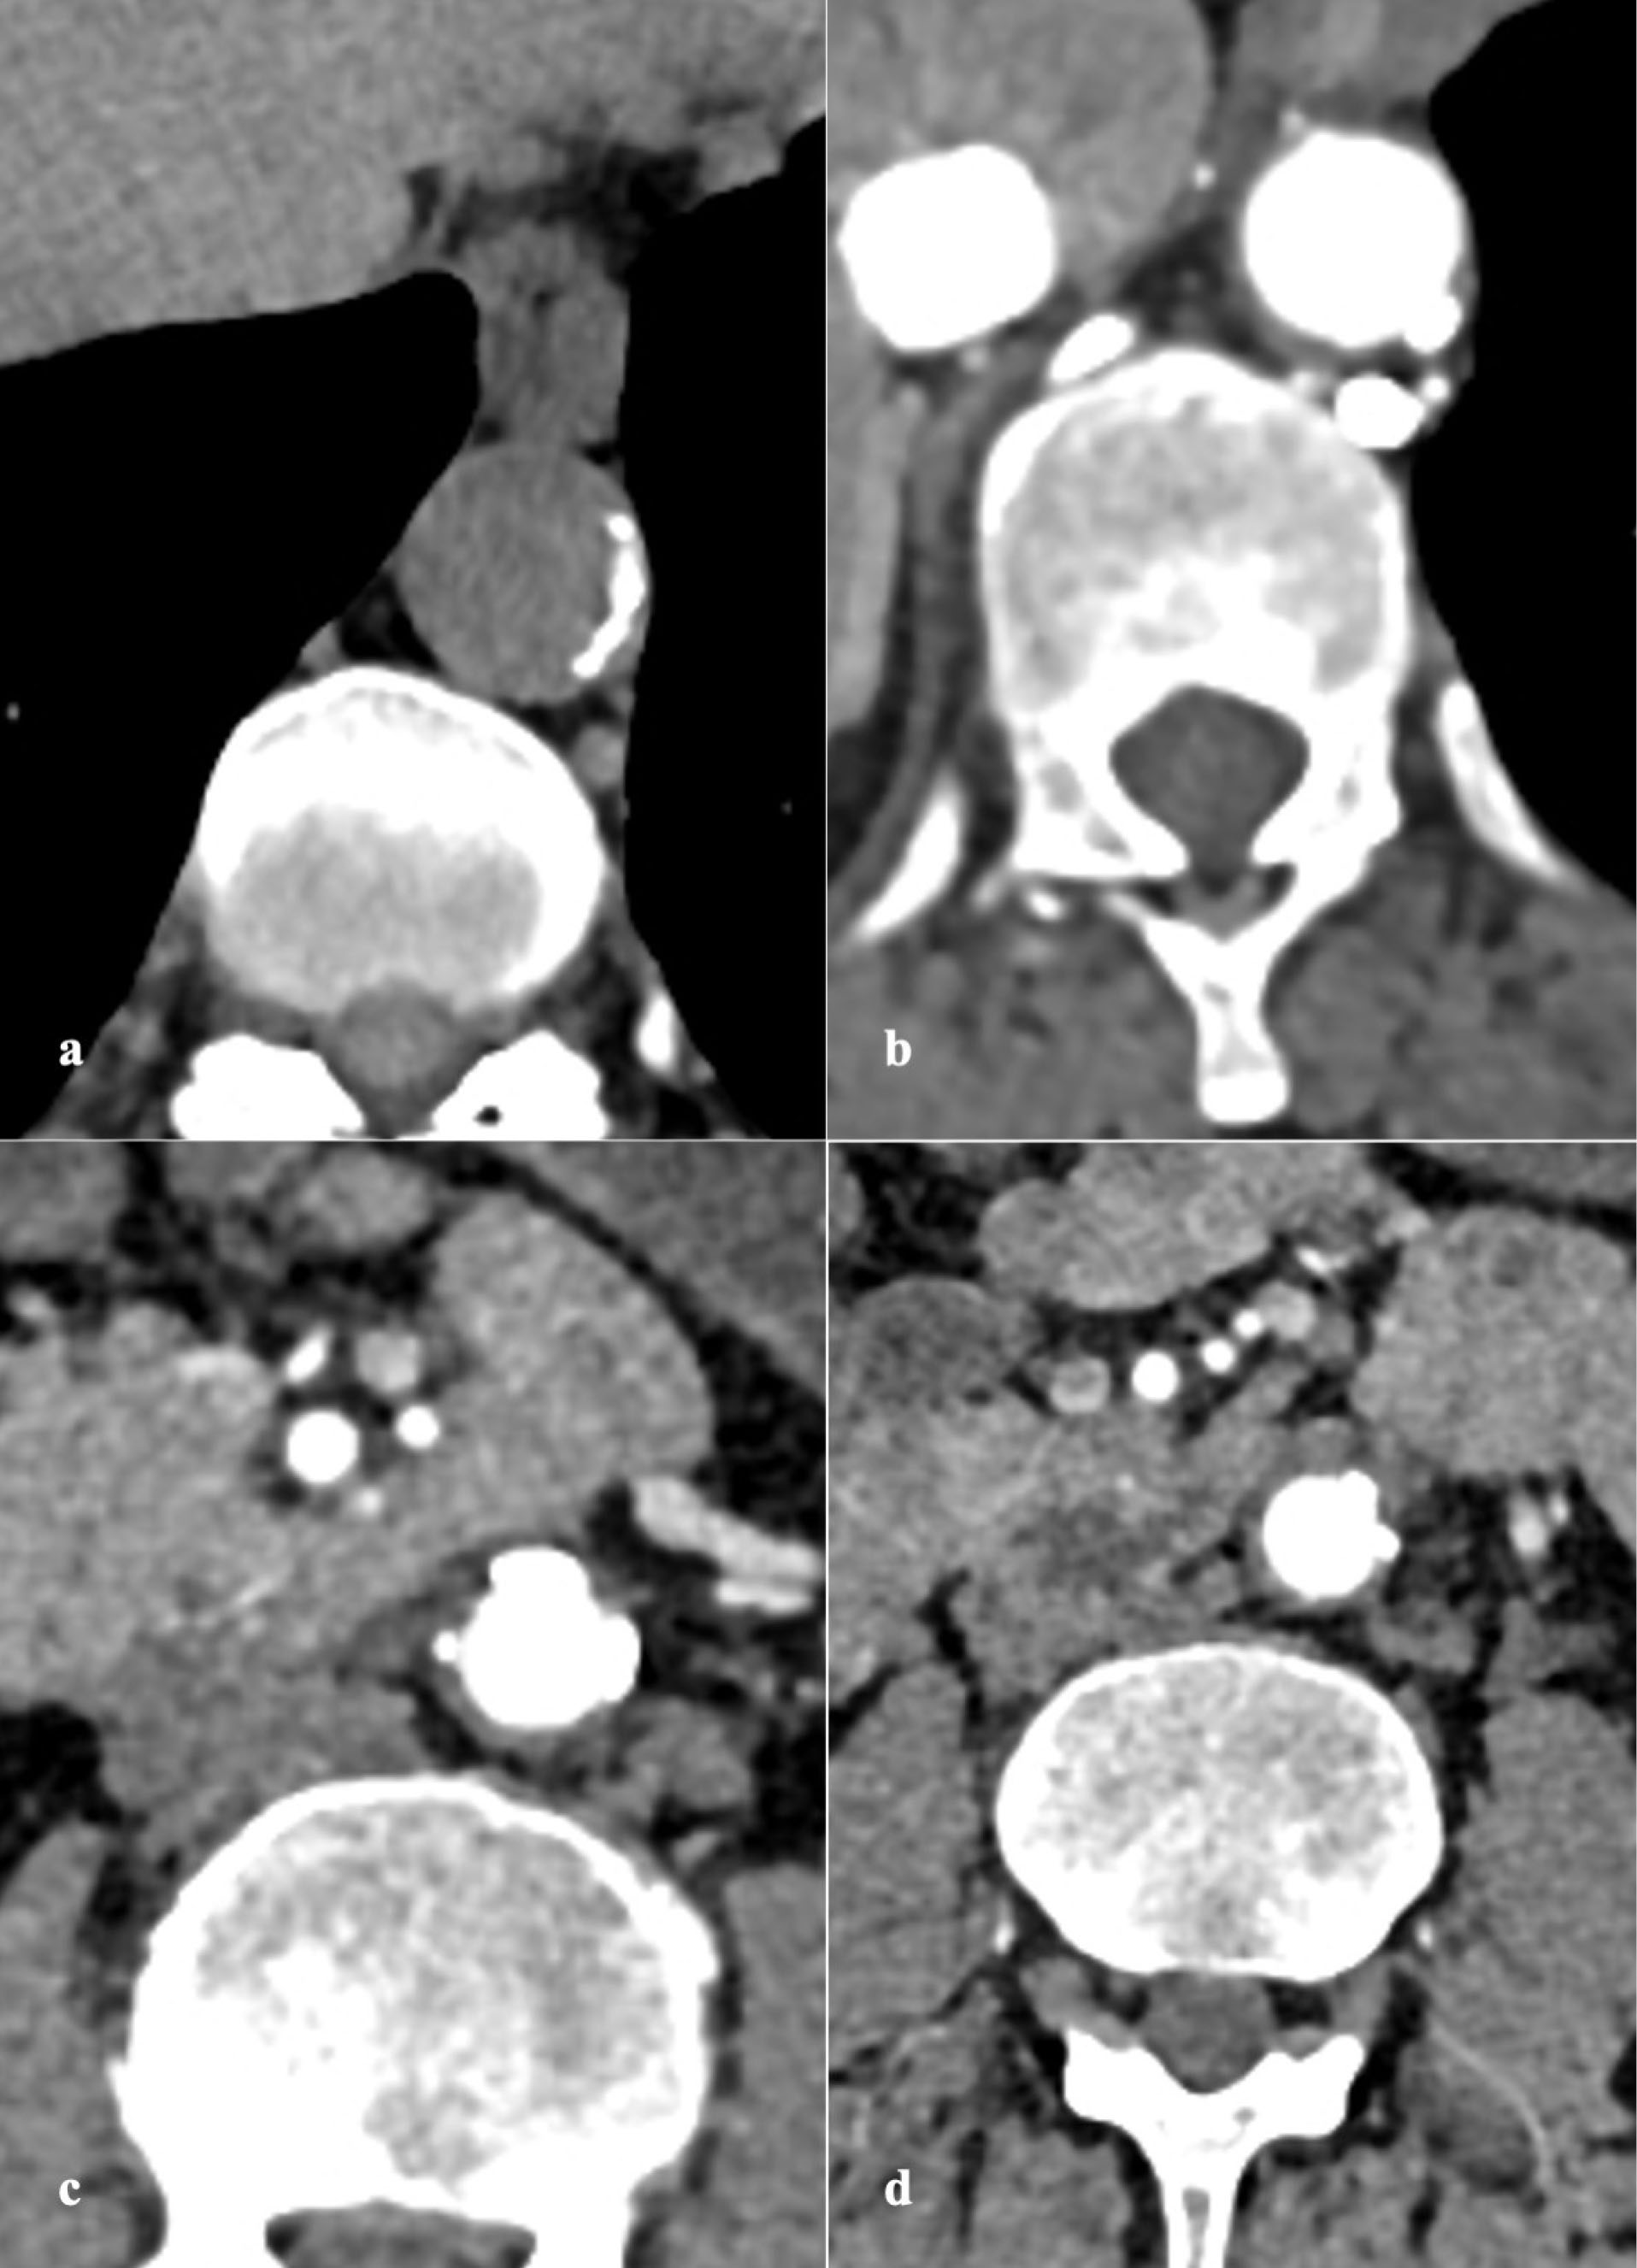

PAU is seen on CTA as contrast filled outpouching (, ) or crater-like morphology on aortography and TEE.

4,6,56

There is invariable surrounding IMH and medially displaced calcified intima ().

Figure 1.

Axial plain (a) CT image shows calcified atherosclerotic wall calcification. Axial arterial phase (b,c,d) CT images reveal multiple contrast-filled outpouchings arising along all walls of the aorta, suggesting penetrating atherosclerotic ulcer

Figure 2.

Coronal (a,b) and Sagittal (c,d) multiplanar reconstructed arterial phase CT images depict the true extent of penetrating atherosclerotic ulcers